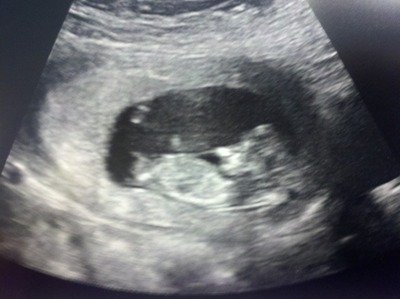

Ok Just had my u/s at 12w4d. She gave me 3 shots but 2 of them look almost exactly the same.

So please let me know what you think!! Be honest..you won't upset or offend me. :)

I thought boy in the first one but girl in the second and third so I am no help at all sorry! I hope you get what you would like

I really think that's a :DD:!!!!

First one looks boy but the last two look girl! So going with girl!